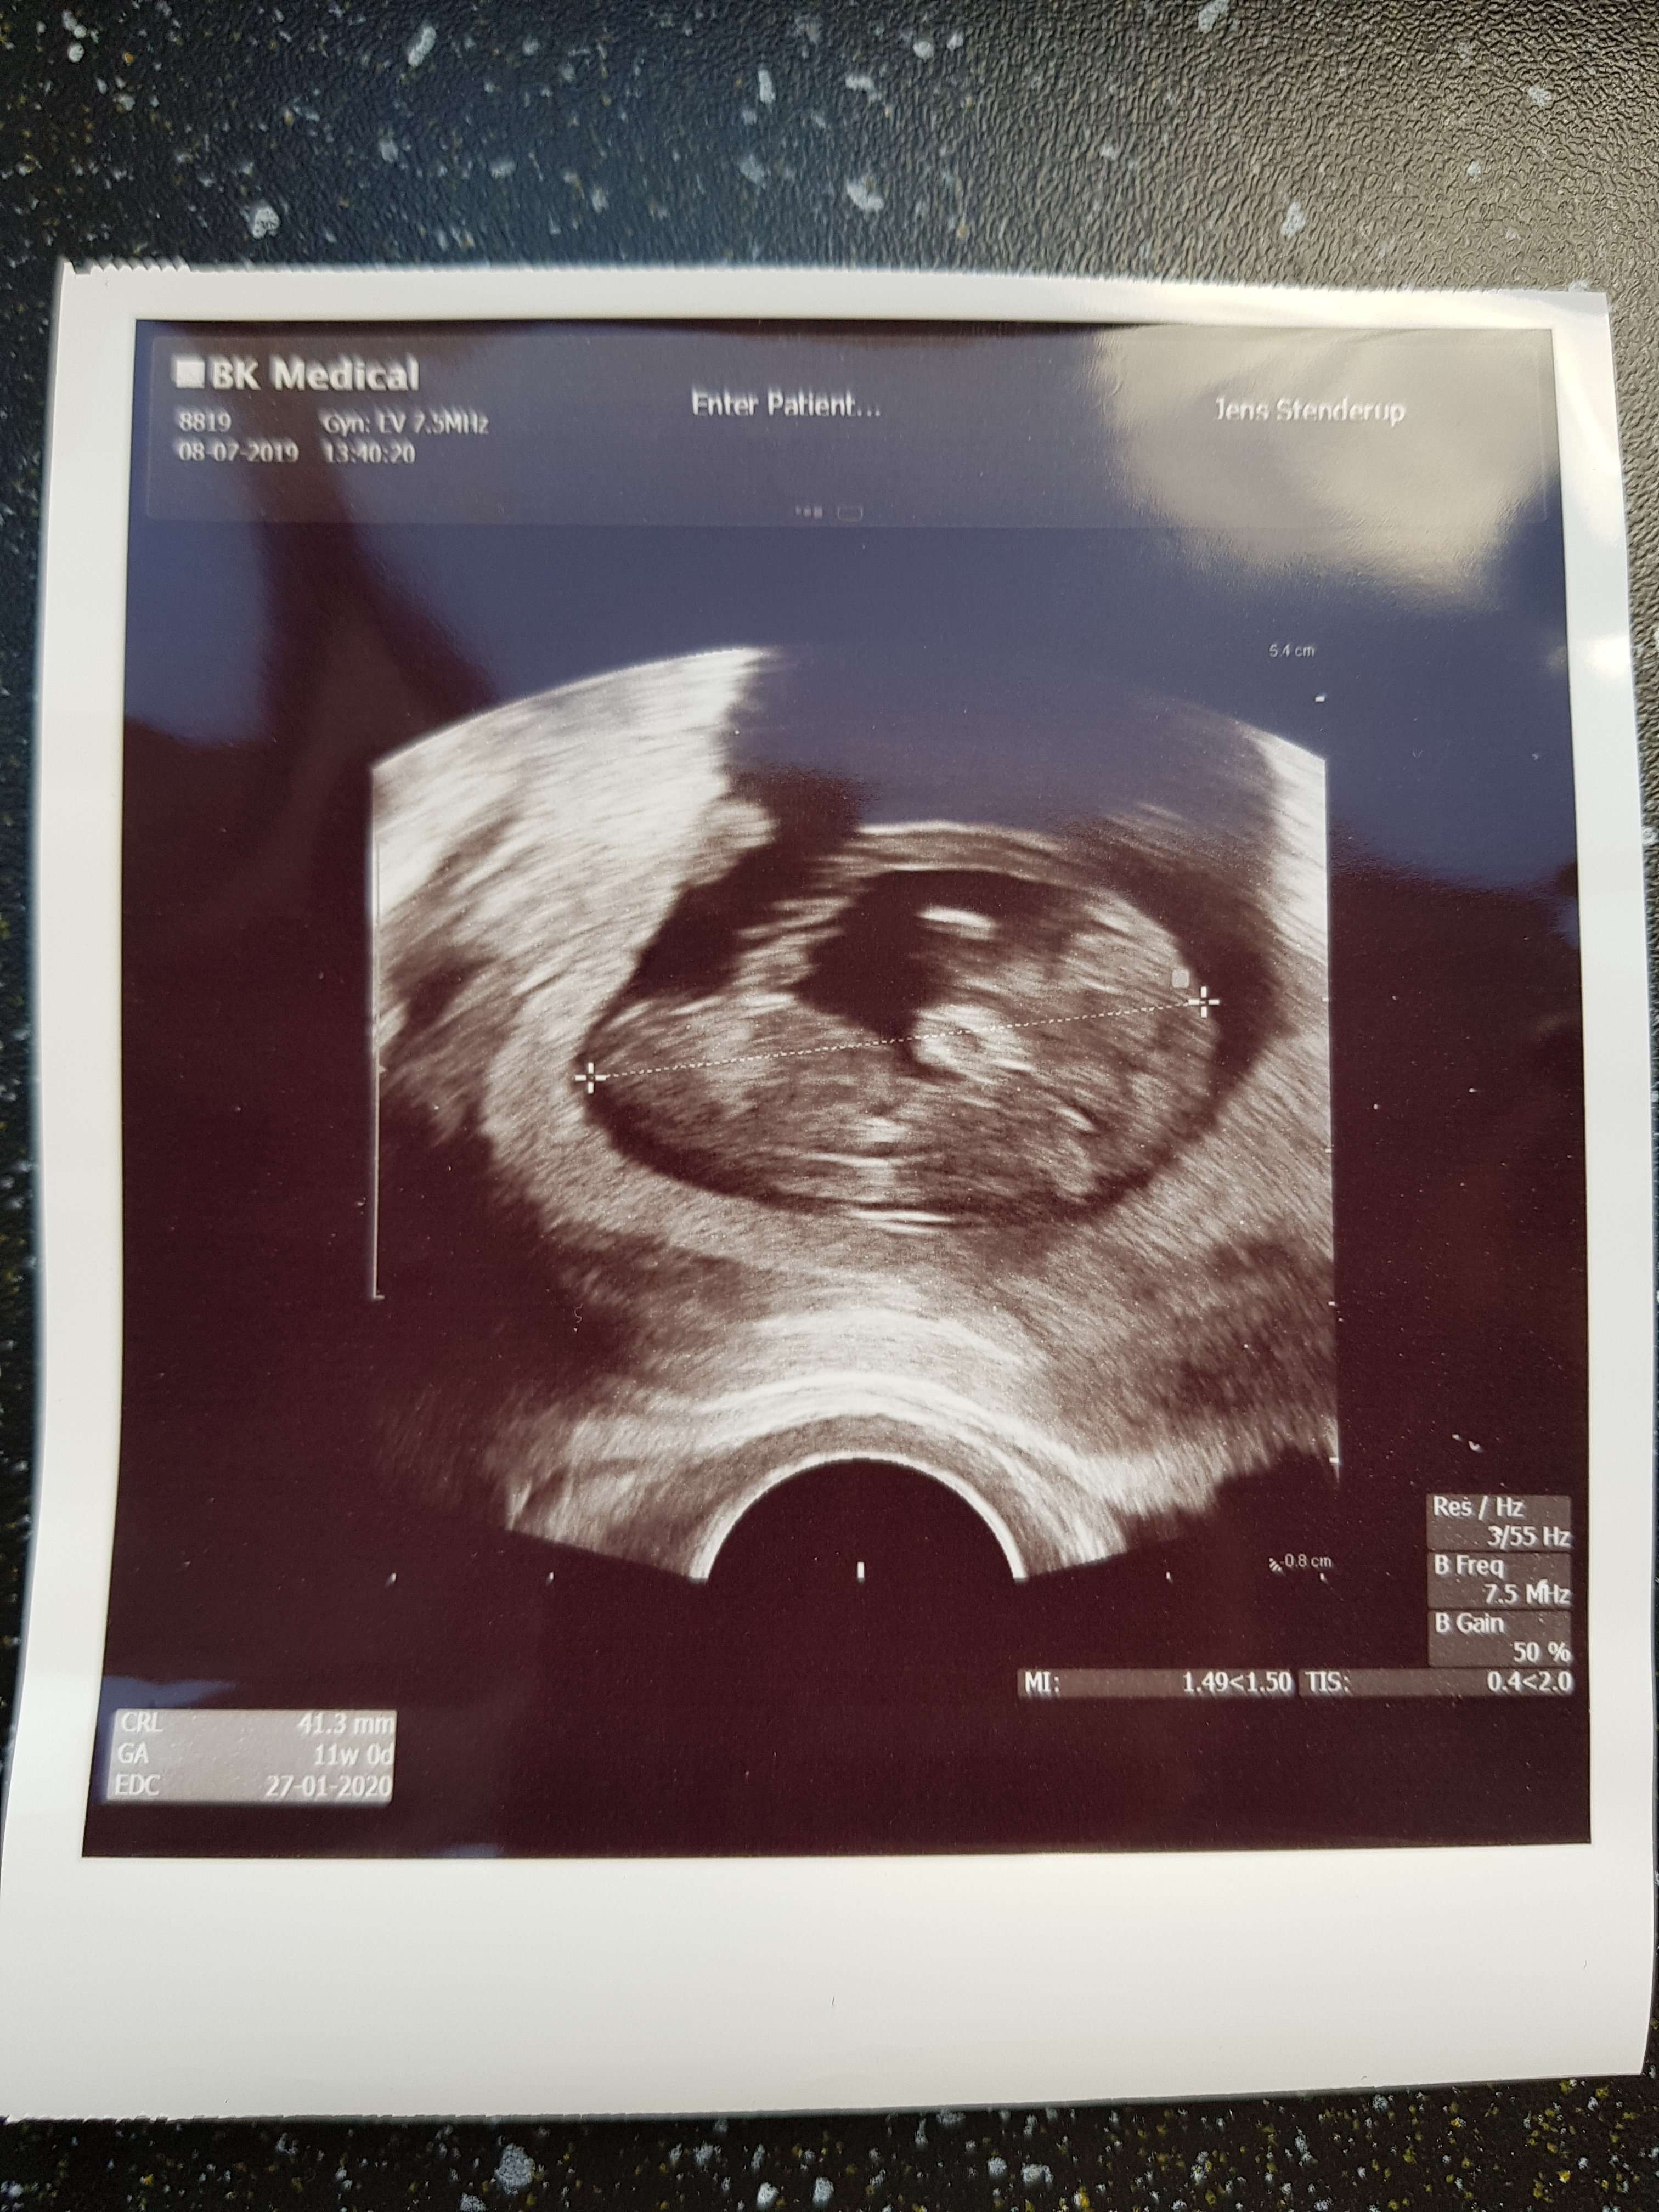

Mam piękna Kruszynkę ♥️ wierciła się, machala nozkami i rączkami ♥️ poplakałam się ze szczęścia! Ma już 41.3mm, wiec wyszło na to, że to już 11+0 tydz. Termin więc przesunął mi się na 27.01 - mam nadzieję że mnie stąd nie wygonicie, ale to zrozumiem, jesli tak Zalaczam pierwsze zdjęcie mojej Kruszynki

Załączniki

• 20190708_172354.jpg

1,6 MB · Wyświetleń: 111

@Søde85 śliczny dzieć [emoji173]️ aż nie mogę się doczekać, kiedy moje takie będzie [emoji16]

Mam piękna Kruszynkę [emoji813]️ wierciła się, machala nozkami i rączkami [emoji813]️ poplakałam się ze szczęścia! Ma już 41.3mm, wiec wyszło na to, że to już 11+0 tydz. Termin więc przesunął mi się na 27.01 - mam nadzieję że mnie stąd nie wygonicie, ale to zrozumiem, jesli tak Zalaczam pierwsze zdjęcie mojej Kruszynki